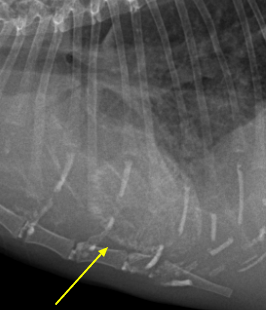

근육 석회화를 유발할 수 있는 질환

- 기타 질환

- 만성 신부전으로 인한 2차적 부갑상선 기능 항진증

- 종양

- 기생충 감염 (톡소포자충증, Neospora, 촌충)